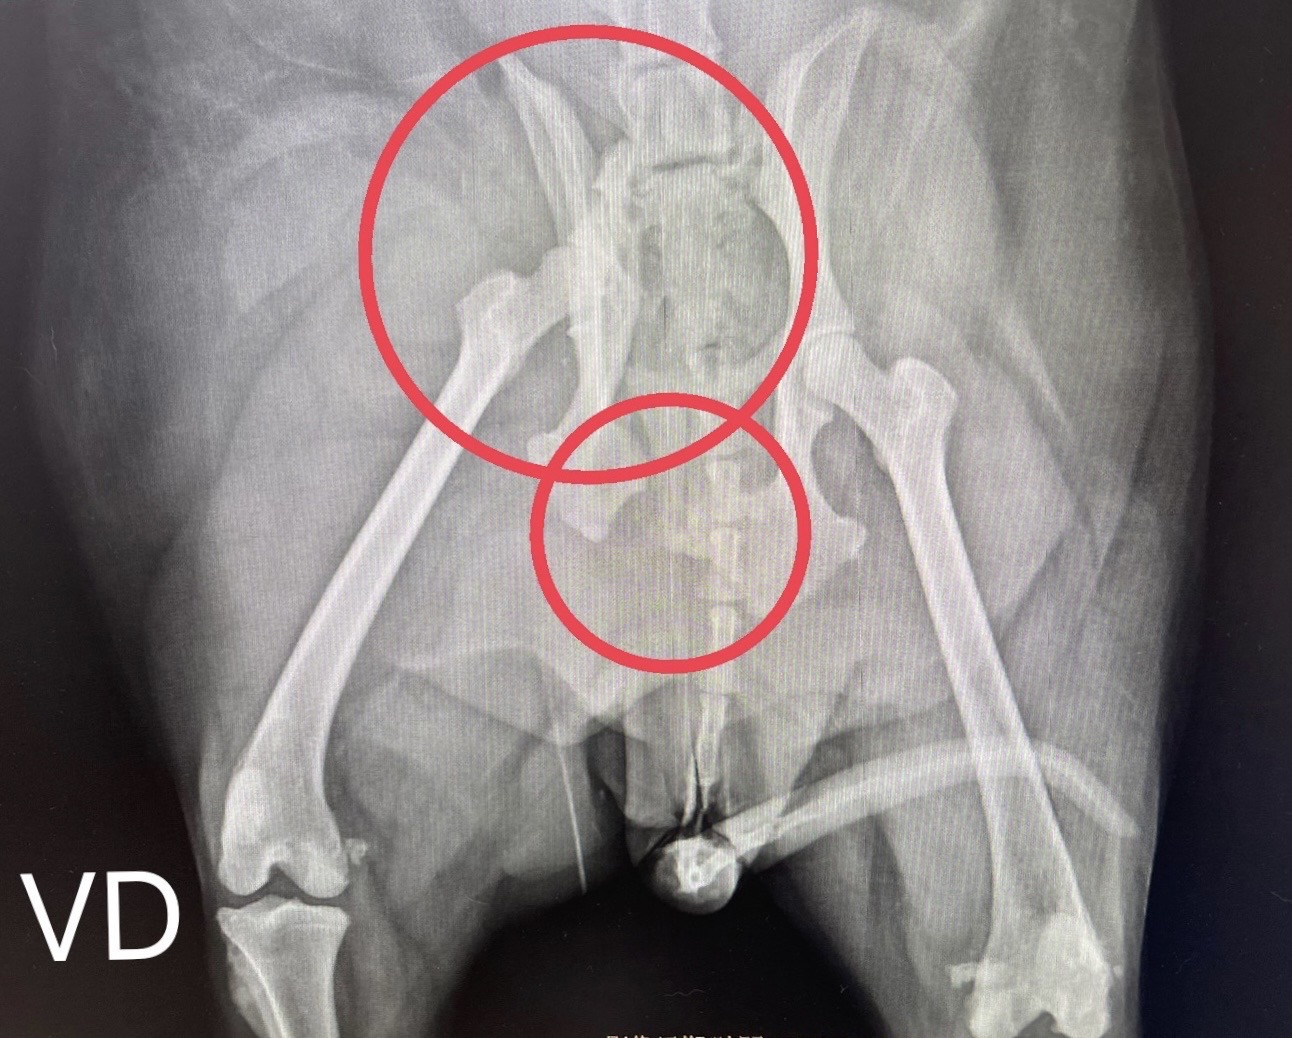

狗狗 車禍 骨盆骨折

狗狗的骨盆骨折相對於常見的四肢骨折 不容易單純靠xray 診斷及擬定手術計畫藉由電腦斷層影像的支援 能提高手術成功的機率

14kg 11歲的莓莓 術後10個月追蹤 行動自如一切正常喔

術前

術後

電腦斷層影像